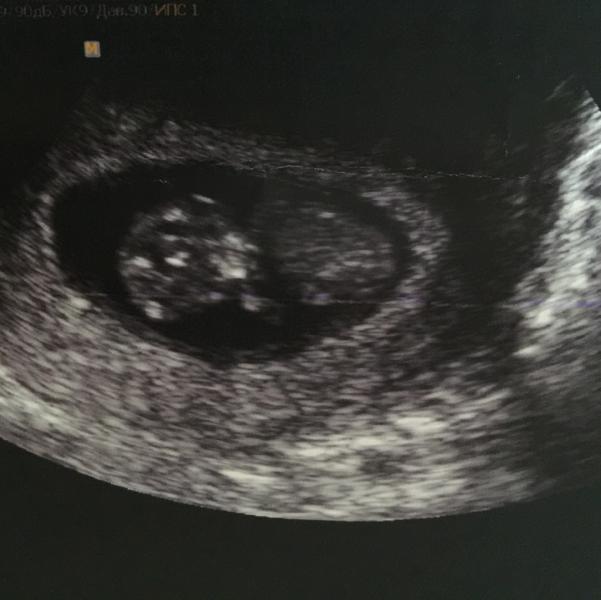

Короче, после приёма у врача помчались на УЗИ, потому что в прошлый раз (была ЗБ) тошнота и "укачивания" прекратились именно в тот самый момент.

На УЗИ сказали, что в...